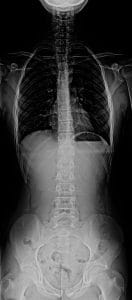

Espinografia normal